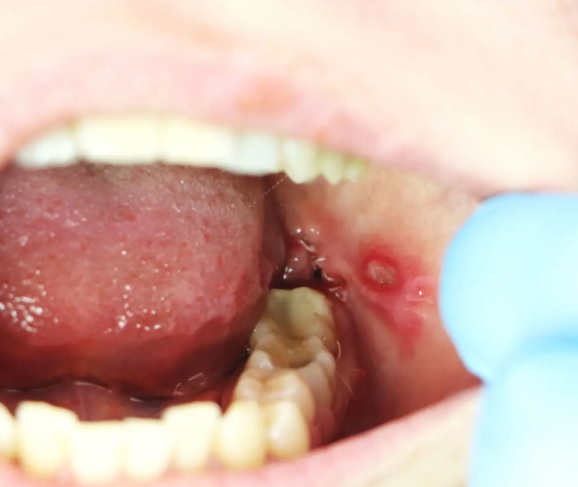

Objawy afty są dość charakterystyczne i rzadko mylone z innymi zmianami w obrębie jamy ustnej. Typowa afta ma postać małego owrzodzenia o białawym lub żółtawym środku, otoczonego wyraźnie zaczerwienioną, zapalną obwódką. Pojawieniu się zmiany zwykle towarzyszy uczucie mrowienia, pieczenia lub swędzenia, które z czasem przeradza się w ból. Bolesność może być nasilona zwłaszcza przy spożywaniu kwaśnych, pikantnych lub gorących pokarmów, a także podczas szczotkowania zębów czy rozmowy. W przypadku aft o większym rozmiarze lub licznych zmian, może dojść do powiększenia węzłów chłonnych oraz stanu podgorączkowego. Utrzymują się zazwyczaj od 7 do 14 dni, jednak nieleczone lub często nawracające mogą świadczyć o innych schorzeniach wymagających diagnostyki.